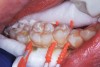

Interproximal insertion of SDF is demonstrated in different patients in Figure 3 through Figure 11. Various diameters and brands of soft dental picks may be used depending on the closeness of the proximal surfaces and ease of insertion; for example, some picks are designed for use in wider spaces between teeth. This protocol also offers versatility. Figure 3, for example, shows the simultaneous use of three thin soft dental picks to saturate proximal surfaces with SDF in a teenaged patient; the treated regions were subsequently covered with fluoride varnish (Figure 4). This patient was initially treated in April 2019 (Figure 5), with an identical re-application 3 months later. As shown in Figure 6, the December 2019 bitewing film revealed good results with the possible exception of the contact regions of the maxillary first and second molars. New SDF application was completed in the December appointment.

Figure 7 illustrates the use of thicker picks in premolar interproximal sites. Additionally, multiple picks can be used in one quadrant or in one proximal site with good isolation to maximize fluid saturation (Figure 9), which the authors have found to be an excellent time-saving strategy. Preventive or interceptive applications of SDF may also be effectively used in interproximal sites in orthodontic patients (Figure 10).

Fig 4. Three thin soft dental picks were used simultaneously for SDF proximal surface saturations in a teenaged patient (Fig 3). After 60 seconds, the treated regions were covered with 5% fluoride varnish (Fig 4). A comparison can be seen of pre-SDF-treatment bitewing films (Fig 5) and 8-month post-SDF bitewing films (Fig 6) for the patient shown in Fig 3 and Fig 4. Radiolucencies were similar or improved, except for contact of maxillary first and second molars.

Figure 4